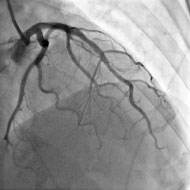

3. The doctor may request for further additional tests, such as a coronary angiogram.